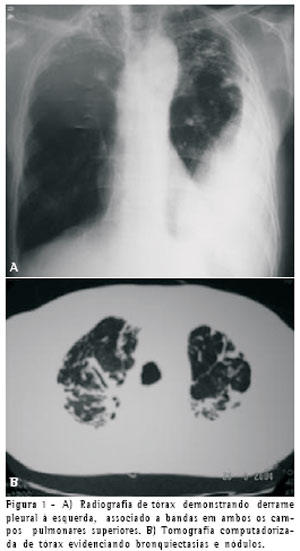

Apresentava hemograma e funções renal e hepática normais. A radiografia e a tomografia computadorizada de tórax evidenciaram derrame pleural à esquerda, associado a bandas, bronquiectasias e nódulos calcificados em ambos os campos superiores (Figura 1).